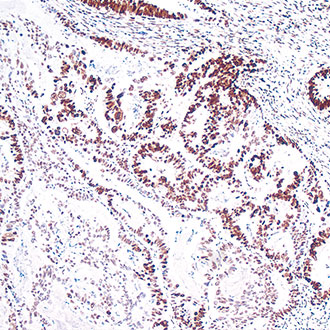

CDX-2

CDX-2 -